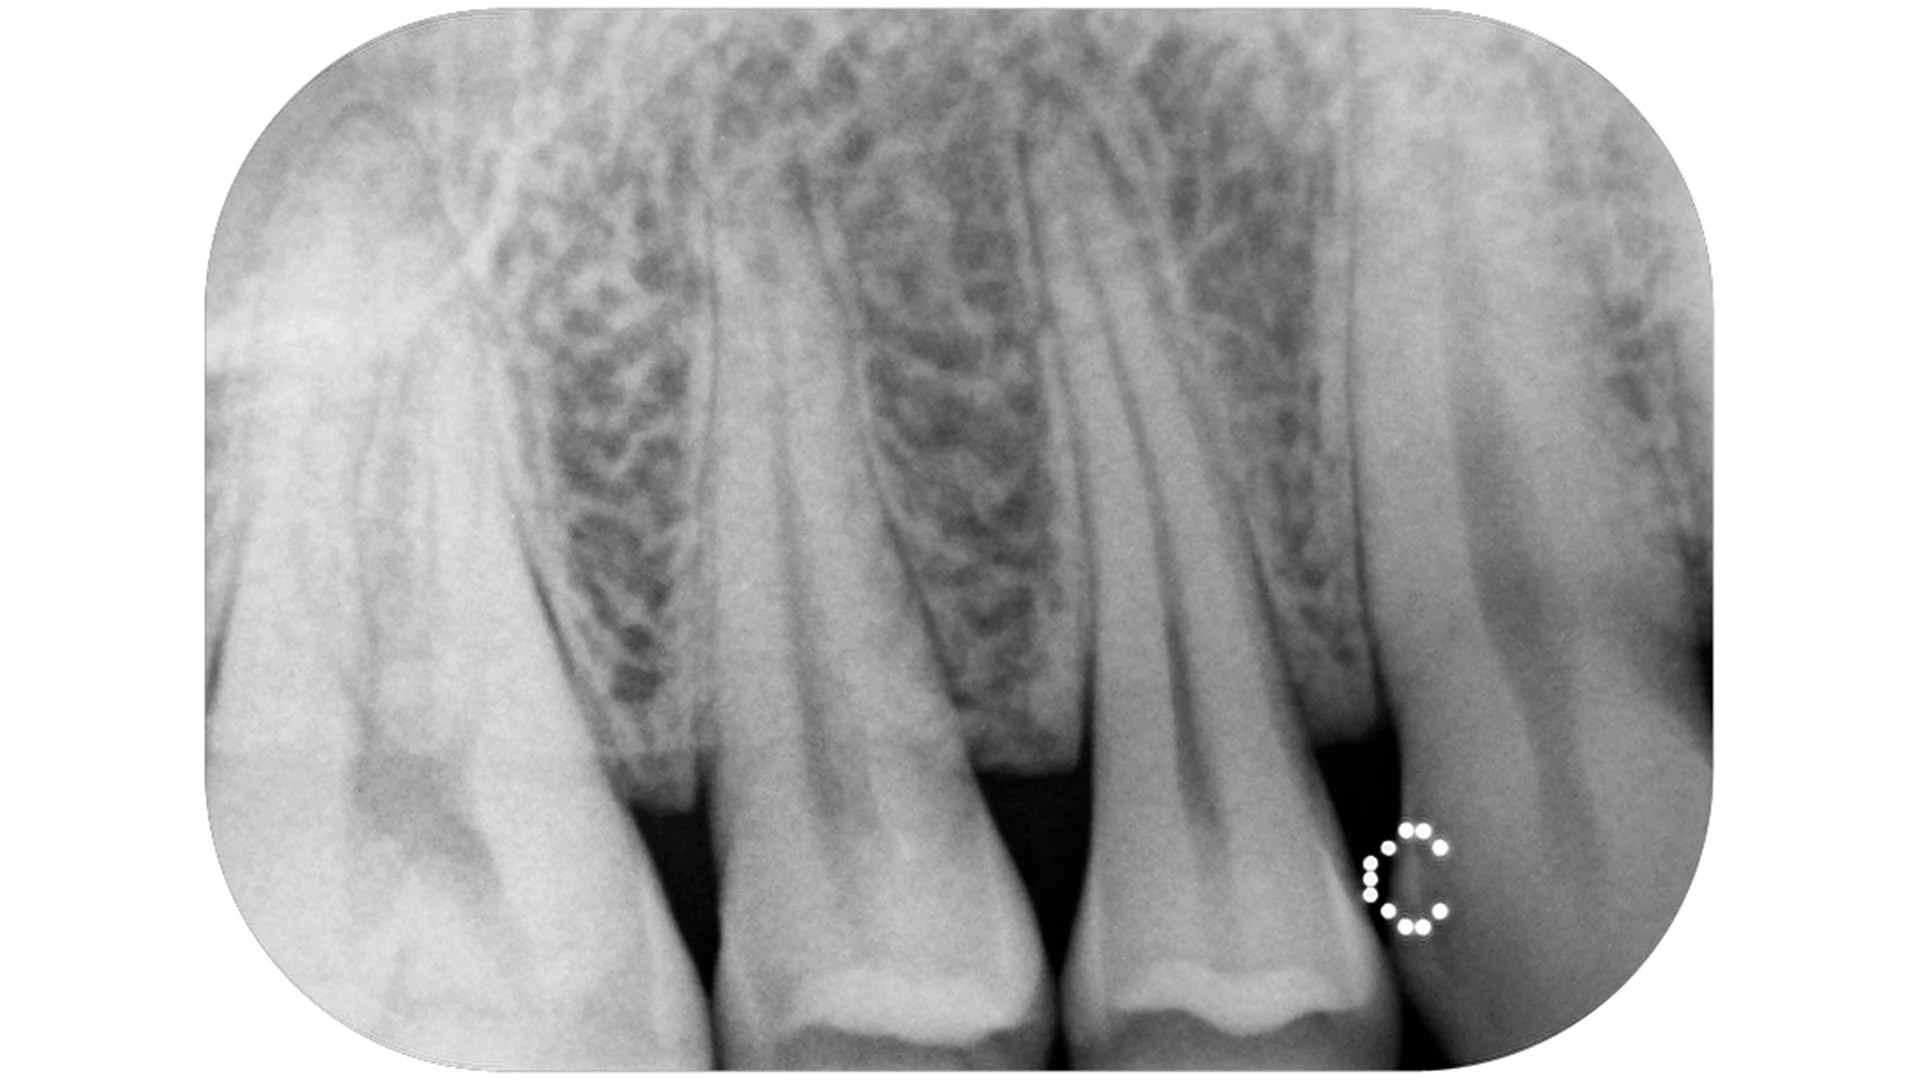

CS 7600 nabízí vše, co očekáváte od vysoce výkonného intraorálního systému záznamu na fólie, tedy rychlost, kompaktnost konstrukce, trvale vysokou kvalitu snímků a kromě toho ještě něco navíc. Naše jedinečná technologie „Exponuj a jdi“ (Scan and Go) automatizuje provoz systému, vylučuje chyby a šetří náklady.

Práce se záznamovými fóliemi je stejně jednoduchá jako s filmem. CS 7600 tedy zachovává pracovní návyky, ale je rychlejší a výkonnější než tradiční snímkování na film. Rutinní vyšetření jsou automatizována a na zabudovaném monitoru lze ihned sledovat úspěšnost vyšetření bez nutnosti odbíhat k počítači.

CS 7600 poskytuje rychle a vysoce kvalitní snímky. První snímek uvidíte do pěti vteřin a skenování a zobrazení statusu je hotovo v několika minutách.

• Vynikající rozlišení obrazu, vysoká rychlost